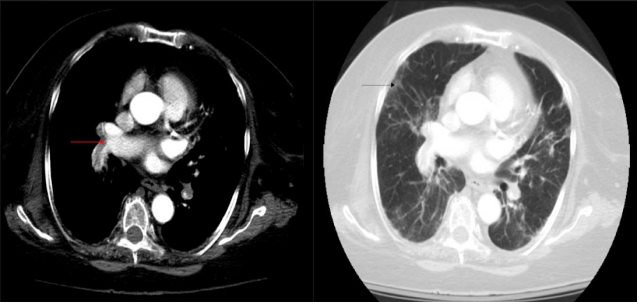

A 55-years old female having no major past medical issues was admitted to the ICU with severe respiratory distress. She had been experiencing symptoms such as fever, shortness of breath, muscle pain, loss of smell and taste for 12 days, and was positive for COVID-19 through a nasal PCR test 8 days ago. At the time of admission, her temperature was high at 102.4F, heart rate was at 114 beats/minute, she was breathing rapidly at 39 breaths per minute, and had low oxygen saturation levels at 81% on room air. Laboratory tests showed an elevated WBC count with low lymphocyte count, mild liver inflammation, increased creatinine levels, high ferritin, lactate dehydrogenase, C-reactive protein, creatine kinase, D-dimer, procalcitonin, troponin, and BNP levels. She was admitted to the ICU. She was started on tocilizumab, hydroxychloroquine, antibiotics, proning, and received enoxaparin prophylactically. Being taken off the ventilator on the 9th day, she had another episode of hypoxia requiring high flow nasal cannula oxygen. On CTPA, filling defects were seen at bifurcation of right and left pulmonary arteries extending into proximal part of all the lobar arteries (Fig.2). Patchy flow is seen in distal lobar and segmental branches. Findings indicated bilateral pulmonary partial thrombosis. Interstitial thickening and GGOs were seen in all lobes of both lungs (Figure 2).

Figure 2: Axial CTPA showed filling defects at bifurcation of right and left pulmonary arteries extending into proximal part of all the lobar arteries (red arrow). Patchy flow is seen in distal lobar and segmental branches. Findings indicated bilateral pulmonary partial thrombosis. Interstitial thickening and GGOs were seen in all lobes of both lungs in axial lung window (black arrow).